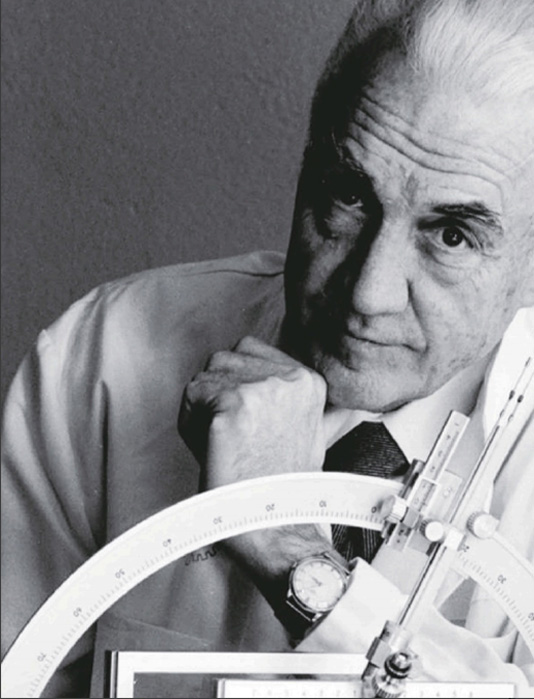

Dr.Lars Leksell教授 (1907-1986)

1949发明Leksell⽴体定向系统,开启微创⽴体神经外科新篇章,1951年发表论⽂⾸次开创性地提出⽴体定向放射外科(SRS)概念,被尊称为“⽴体定向放射外科之⽗”。

改变历史的科学巨匠

"外科医⽣的⼿术器械必须符合其任务的需要,⽽就⼈脑⽽⾔,再精细都不为过"。

Dr.Lars Leksell教授 (1907-1986)

1949发明Leksell⽴体定向系统,开启微创⽴体神经外科新篇章,1951年发表论⽂⾸次开创性地提出⽴体定向放射外科(SRS)概念,被尊称为“⽴体定向放射外科之⽗”。

改变历史的科学巨匠

"外科医⽣的⼿术器械必须符合其任务的需要,⽽就⼈脑⽽⾔,再精细都不为过"。